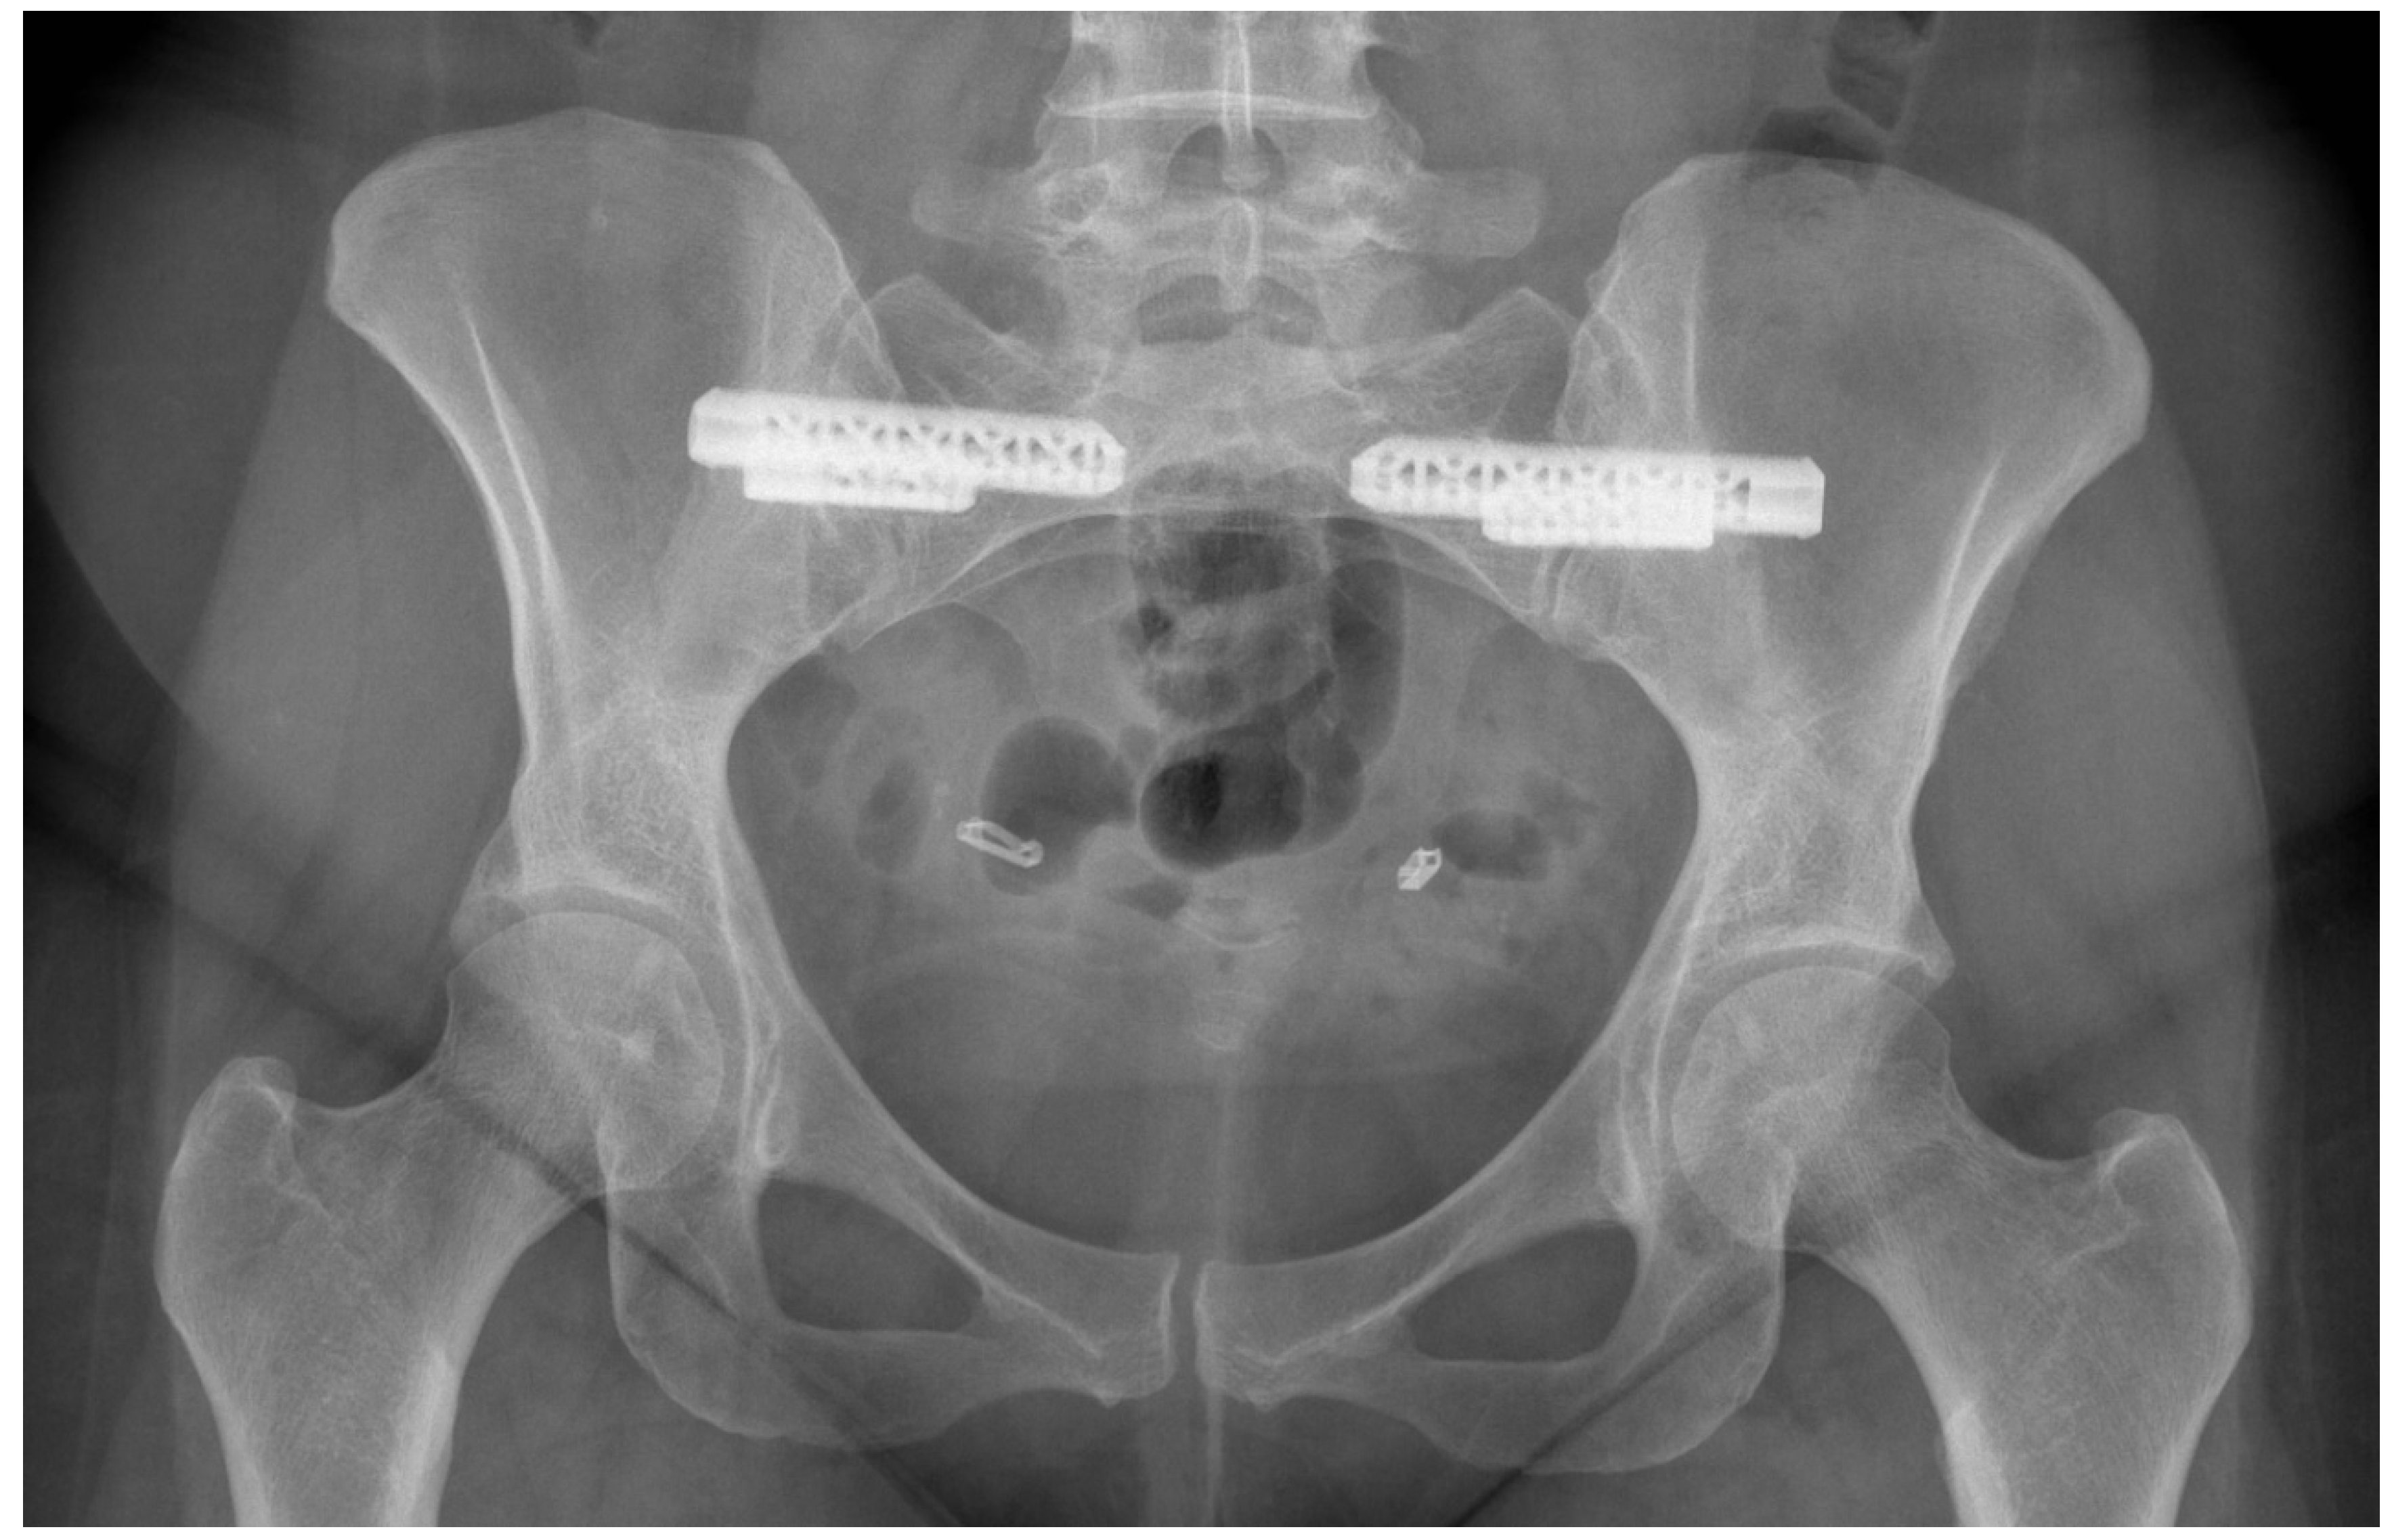

- Belanger, T.A.; Dall, B.E. Sacroiliac arthrodesis using a posterior midline fascial splitting approach and pedicle screw instrumentation: A new technique. J. Spinal Disord. 2001, 14, 118–124. [Google Scholar] [CrossRef] [PubMed]

- Van Zwienen, C.M.; Van den Bosch, E.W.; Snijders, C.J.; Van Vugt, A.B. Triple pelvic ring fixation in patients with severe pregnancy-related low back and pelvic pain. Spine 2004, 29, 478–484. [Google Scholar] [CrossRef] [PubMed]

- Kibsgård, T.J.; Røise, O.; Sudmann, E.; Stuge, B. Pelvic joint fusions in patients with chronic pelvic girdle pain: A 23-year follow-up. Eur. Spine J. 2013, 22, 871–877. [Google Scholar] [CrossRef] [PubMed][Green Version]

- Kibsgård, T.J.; Røise, O.; Stuge, B. Pelvic joint fusion in patients with severe pelvic girdle pain—A prospective single-subject research design study. BMC Musculoskelet. Disord. 2014, 15, 85. [Google Scholar] [CrossRef] [PubMed]